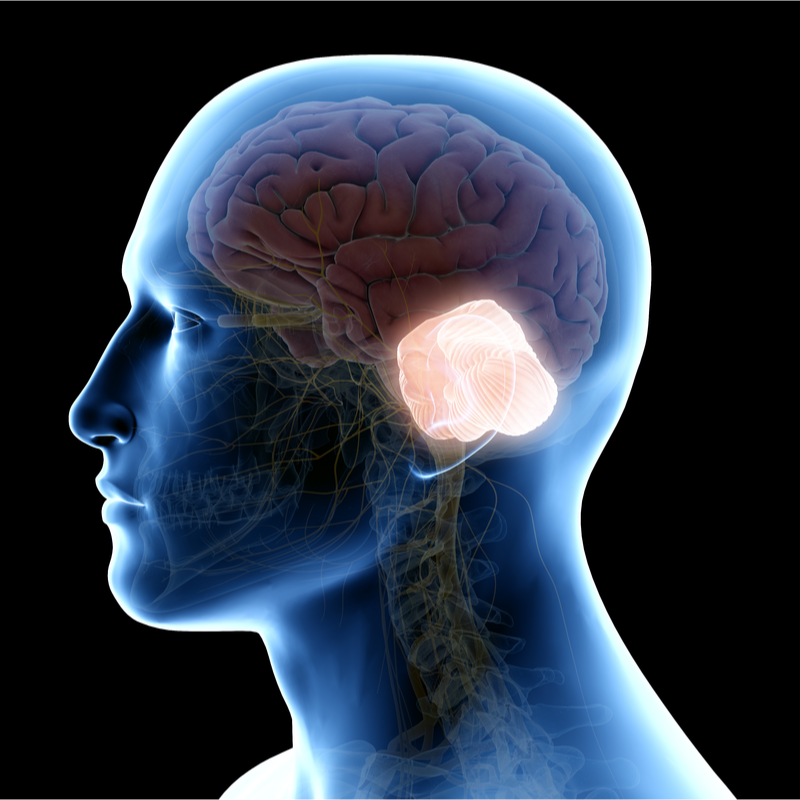

Smadzeņu audzējs

Ļaundabīgs smadzeņu audzējs

Medulloblastoma